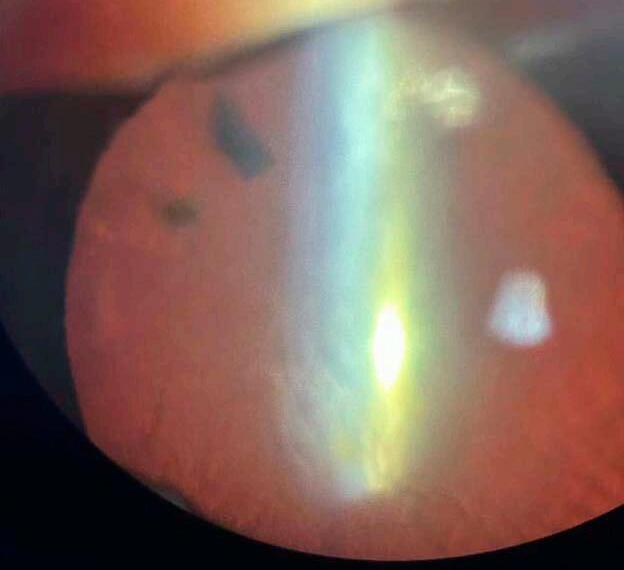

7. Casos desafiantes y estrategias adaptativas

Veremos a continuación ejemplos prácticos, ya que una cosa es elegir la lente perfecta en una cirugía estándar y otra muy distinta es decidir en el “campo de batalla” cuando la bolsa capsular se rompe, la zonulación se debilita o un paciente llega con múltiples antecedentes quirúrgicos. Es ahí donde la tecnología debe ceder espacio al criterio quirúrgico y la planificación se transforma en adaptación.

Revisión narrativa sobre lentes intraoculares en evolución: de la precisión óptica a la experiencia visual personalizada.

7.a La pseudoexfoliación capsular: la fragilidad como constante

Uno de los escenarios que más respeto me genera —y que más frecuentemente encuentro en la práctica diaria— es el de la pseudofoliación, como la literatura científica también lo ha demostrado. 44,45 Cápsulas que parecen estables pero colapsan al menor movimiento, zonulólisis subestimadas en las imágenes preoperatorias, y pupilas rígidas que complican cada paso.

En estos casos, prefiero anticiparme. Si la sospecha es alta, elijo lentes con buena estabilidad háptica, evito implantes premium complejos y tengo siempre listo un anillo de tensión capsular. Me ha tocado, más de una vez, modificar la estrategia intraoperatoriamente, eligiendo una lente monofocal en sulcus con óptica capture para asegurar centrado y funcionalidad.

7.b Rotura capsular: del susto al rescate ordenado

Si bien hay una vasta recopilac ión de información y evidencias acerca de factores que pueden predisponer una ruptura capsular, como también de posibles soluciones intraquirúrgicas ante la aparición de la complicación, 46-48 creo que un interesante aporte es compartir experiencias: en una cirugía reciente, un paciente con alta miopía y cápsula muy elástica terminó con una dehiscencia posterior en la fase final del faco. La lente planificada era una EDOF tórica. Ante la situación, utilicé una técnica mixta: realicé una captura óptica con una lente de 3 piezas, utilizando los restos del borde anterior como soporte, y logré un centrado perfecto. Ese caso, como tantos otros, me recuerda que la tecnología es útil, pero la técnica salva cirugías.

8. Nuevas fronteras: lentes ajustables, ópticas líquidas y plataformas inteligentes

Vivimos una época donde la frontera entre lo posible y lo clínicamente viable se vuelve cada vez más difusa. La investigación y desarrollo en lentes intraoculares ha entrado en una fase de disrupción tecnológica, donde conceptos como ajuste postoperatorio, biomateriales activos y procesamiento inteligente de luz ya no pertenecen solo a los papers, sino que comienzan a asomar en la práctica clínica, como veremos en algunos ejemplos a continuación.

8.a Lentes ajustables con luz: precisión postoperatoria real

Las Light-Adjustable Lenses (LAL) representan uno de los avances más concretos en esta nueva era. 50,51 Su promesa es contundente: corregir hasta el último decimal refractivo después de la cirugía, mediante luz ultravioleta. Esto permite modificar el poder de la lente una vez que el ojo ha cicatrizado, algo impensado hace solo unos años.

Aunque aún no están disponibles en todos los países y su implementación requiere equipamie nto especializado y protocolos estrictos de fotoprotección, son una ventana al futuro de la cirugía refractiva intraocular. En pacientes con antecedentes de cirugía refractiva o topografía s impredecibles, la posibilidad de refinar el resultado posoperatorio con tanta precisión abre un escenario completamente nuevo. 51

8.b Ópticas líquidas y lentes biomiméticas

7.c Ojos previamente operados: topografía difícil, expectativas altas

Otro desafío frecuente son los ojos con cirugía refractiva previa, donde las fórmulas tradicionales pierden eficacia y el cálculo de la LIO casi “se convierte en una apuesta”. En mi caso, para realizar el cálculo de la lente, recurro a múltiples plataformas biométricas, comparo predicciones y busco consenso entre ellas. Es real que el margen de error es mayor y que hay que manejar con el paciente las expectativas de entrada, explicándole de antemano las características “difíciles” de sus ojos.

Otro campo prometedor es el de las ópticas líquidas: lentes que pueden modificar su forma o su índice de refracción mediante estímulos internos o externos y que además incluso pueden incorporar y liberar fármacos co n diversas func iones dentro del ojo. 52 Aunque todavía en etapas de experimentación, estas tecnologías buscan emular la acomodación natural, un objetivo que ha sido el “Santo Grial” de la oftalmología moderna.

En lente, platafor hay expectativas veces una

En paralelo, se investigan lentes con memorias adaptativas, 52 que responden a cambios de temperatura, presión o medios químicos intraoculares, para ajustar su comportamiento óptico según el entorno del ojo. Son materiales “inteligentes” que integran la lógica de la bioingeniería con la necesidad quirúrgica.

8.c Plataformas inteligentes y personalización total

En lo personal a veces elijo una EDOF no tórica en lugar de una trifocal para ganar tolerancia. O incluso una monofocal segmentada, si el ojo tiene cicatrices corneales o aberraciones elevadas. En estos contextos, la tecnología ayuda y aunque es cierto que también existen lentes diseñadas más específicamente para casos difíciles como estos, que tienen una óptica estenopeica,49 lo relevante para el cirujano está en saber cuándo adaptarse, cuándo simp lificar y cuándo renunciar a lo ideal para garantizar lo seguro.

específica mente tienen

La inteligencia artificial y el big data clínico ya se están integrando a los cálculos de LIOs. 54 Plataformas que cruzan millones de datos biométricos, curvas de desenfoque y experiencias quirúrgicas previas para predecir el resultado más probable, adaptado a cada paciente.

INFORME ESPECIAL

Aunque aún estamos lejos de una “lente personalizada” impresa bajo demanda para cada ojo —como promete la bioimpresión 3D—, el concepto de personalización total ya está en marcha: no solo en el diseño óptico, sino en la predicción de adaptación, satisfacción y expectativa visual futura. Mirando hacia adelante, lo que se perfila no es solo una nueva generación de lentes, sino una nueva forma de pensar la cirugía del cristalino: más precisa, más flex ible, más adaptada a cada individuo. Pero también, más exigente para nosotros, los cirujanos, que debemos aprender a dominar tecnologías sin perder de vista lo esencial: el ojo, el paciente, y el acto quirúrgico como encuentro humano.